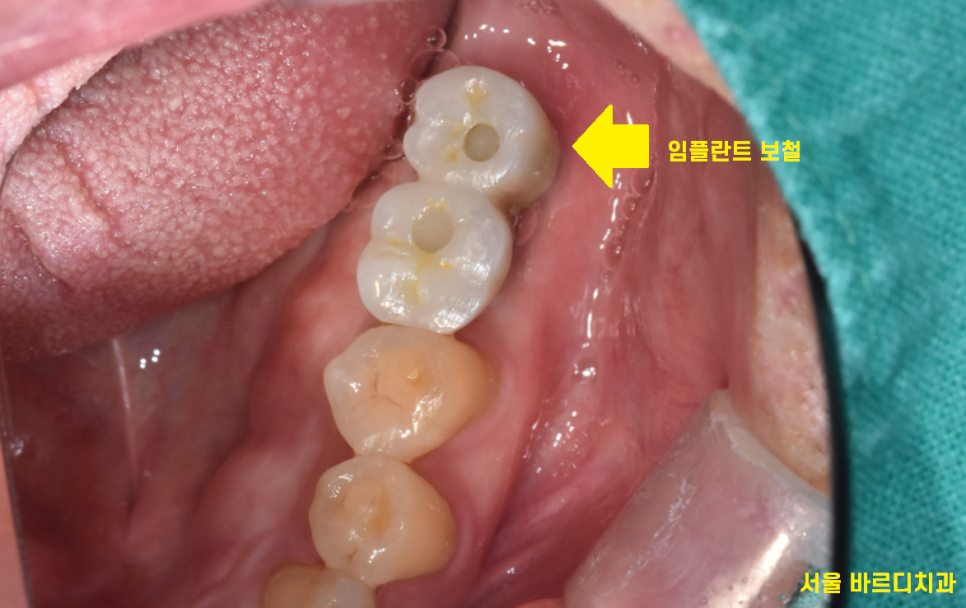

막상 시간이 되어

임플란트 완성을 해드리면

임플란트 보철 불편하다고 오시는 분들이 많습니다.

제일 많이 호소하시는 것이

- 볼 씹음

임플란트 보철 완성 후

두번째로 임플란트 보철 불편한

원인 중 하나는

애초에 잘못 만들어 졌을 수도 있습니다.

일반적으로 윗니가 아랫니를 덮게 되는 형태인데

이런 형태가 되었을 때

저작

씹는 운동을 시행할 때

볼을 밀어내기 때문에

볼 씹힘 발생하지 않습니다.